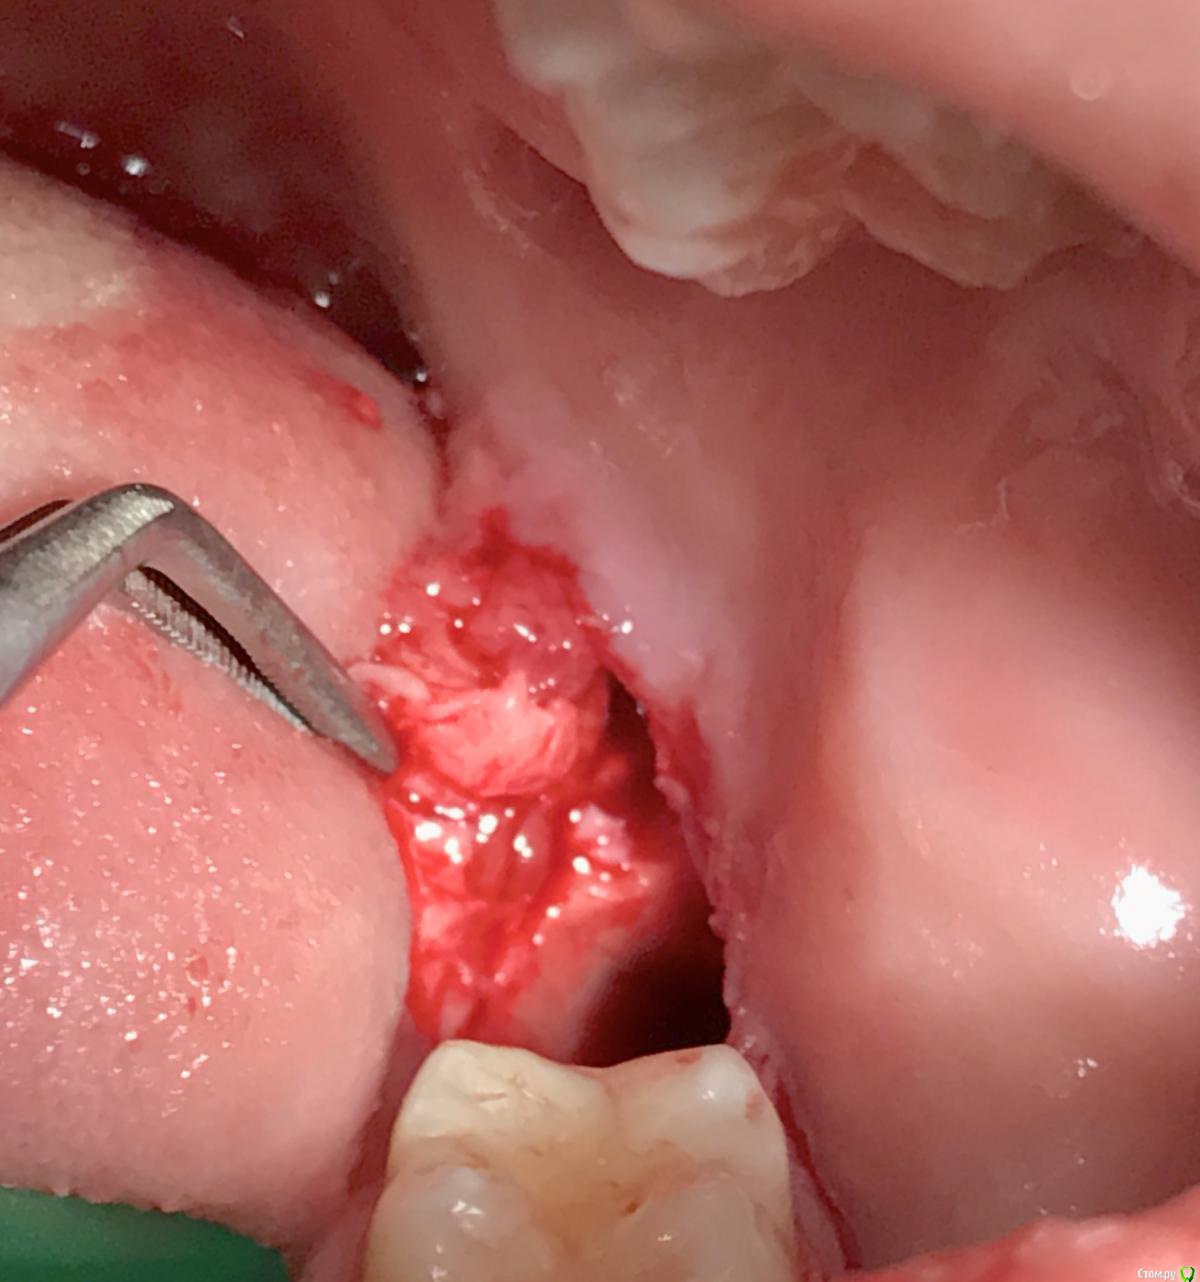

колесников Опубликовано 2 апреля, 2017 Автор Поделиться Опубликовано 2 апреля, 2017 Тройной лоскут , вид через 5 -7дней. Снимок "до". И благодарность за скорое заживление 6 Ссылка на комментарий

колесников Опубликовано 3 апреля, 2017 Автор Поделиться Опубликовано 3 апреля, 2017 Раньше я тоже думал,что если пациент не пришёл на осмотр,"пропал",то у него все хорошо. На самом деле у него все плохо и он пошёл к другому врачу. Расщеплённый лоскут надо зафиксировать,о чем собственно и пост,он как минимум усадку даст,как максимум частично некротизируется без питания.Кетгут не самый лучший шовный в этом случае,швы будут не состоятельны на третий день,а лоскут нестабилен будет до 7-9 дней,угроза вторичного инфицирования из-за расхождения краев. Ссылка на комментарий

колесников Опубликовано 6 мая, 2017 Автор Поделиться Опубликовано 6 мая, 2017 Воспользовался случаем попрактиковаться в выделении язычного лоскута. Разрез поверхностный,далее расщепление и выделение.По поводу лоскута без графта. Дважды пришлось так поступить. В первом случае расхождение краев за 7кой с образованием щели и застревание пищи. Во втором случае мезиально все герметично,дистально (?) щель,при зондировании -пусто. Итого: лоскут без графта-так себе вариант. Ссылка на комментарий